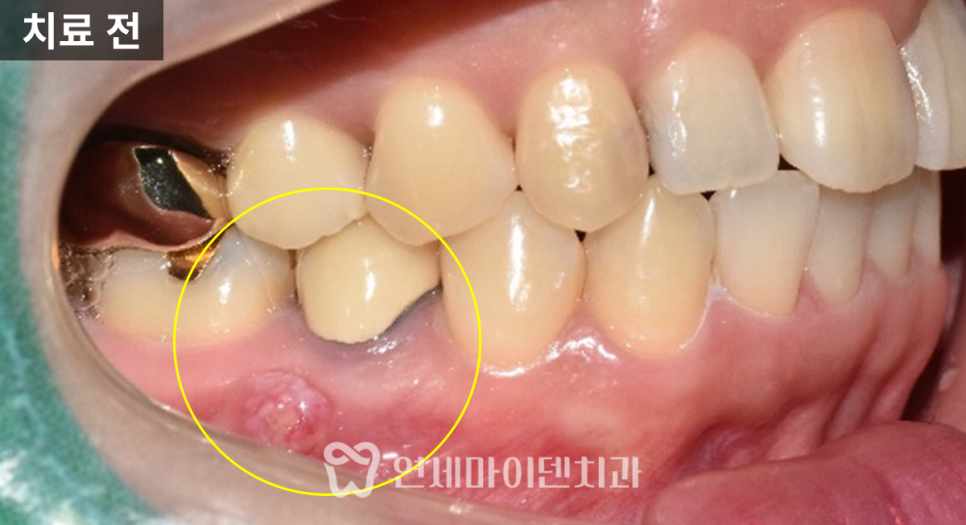

오늘 소개해드릴 케이스는

과거 신경치료를 받았던 치아에서

잇몸에 고름이 주기적으로 생긴 경우입니다.

통증은 심하지 않았지만, 잇몸 색이 변하고

고름이 올라왔다가 사라지기를 반복했습니다.

오랜 기간 방치하면서 뼈가 많이 녹아 있었고,

반대편 치아도 비슷한 문제로 발치한 상태였습니다.